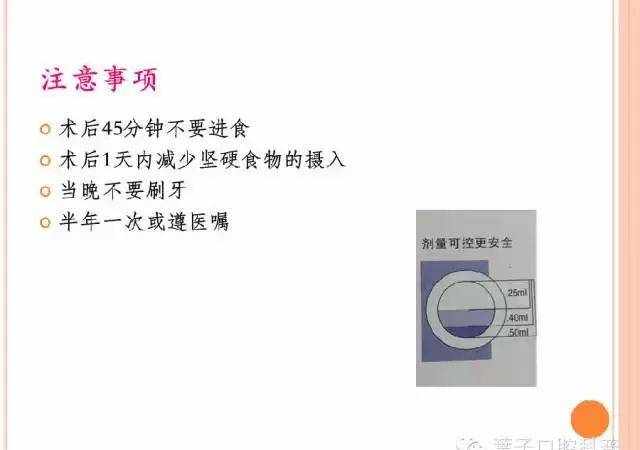

窝沟封闭

窝沟封闭又称点隙裂沟封闭(pit and fissure sealant),是指不去除咬合面牙体组织,在其上涂布一层粘结性树脂,保护牙釉质不受细菌及代谢产物侵蚀,增强牙齿抗龋能力,从而达到预防龋病发生的一种有效防龋方法。

1.为什么要进行窝沟封闭?

窝沟封闭最重要的作用就是可以避免发生龋齿。饮用水中的氟可以保护牙齿的光滑面,但后牙需要额外的保护。

窝沟封闭剂保护后牙咬合面上的细小窝沟,把食物和细菌隔绝在外。在牙齿龋坏以前给牙齿涂上封闭剂就能有效避免龋坏,从而大大地为患者节约了治疗时间和金钱。

2.几岁做窝沟封闭?

最佳进行窝沟封闭的年龄是3岁-乳磨牙、6岁-第一恒磨牙、12岁-第二恒磨牙。其它窝沟较深的牙齿也可以做窝沟封闭。

另外,有些易患龋的成年人也需要做窝沟封闭。

3.做了窝沟封闭,就不再怕蛀牙了吗?

窝沟封闭不是一劳永逸的,预防蛀牙仍然需要好好刷牙,用牙线,定期看牙医检查。

而且,窝沟封闭后也需要定期复查(六个月一次),保证其没有脱落或磨损。如果有问题,牙医可以对它再次做封闭。

4.窝沟封闭怎么做?

很多家长会担心孩子不配合进行窝沟封闭,但是,做窝沟封闭是没有疼痛感觉的,只要给予引导,孩子大多都能接受。

家长还可以提前在家让孩子认识窝沟封闭的过程,其实就是“给牙齿穿上一件新衣服”这么简单。

1.清洁牙面

2.把牙面冲洗干净,干燥牙面

3.涂液体材料让牙齿表面变粗糙

4.再次冲洗干净,干燥牙面

5.涂窝沟封闭剂

6.用特殊光照,使窝沟封闭剂变硬